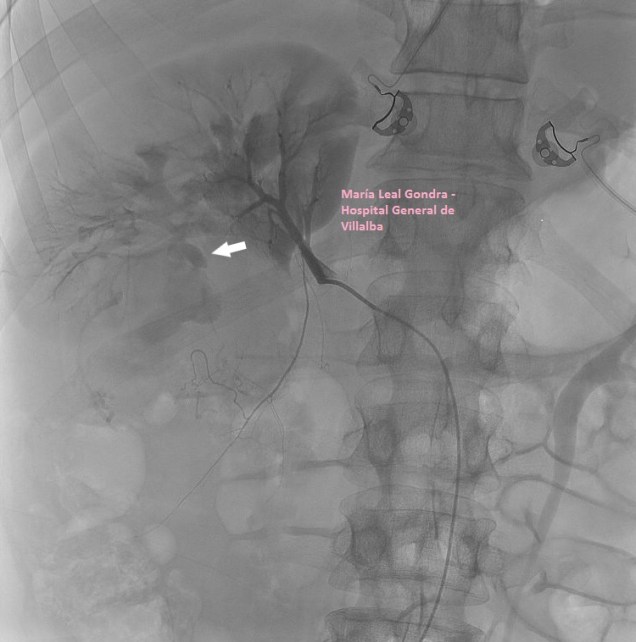

Se realiza Tc con contraste para completar estudio de extensión, en el que se confirman los hallazgos visualizados en la ecografía incluido el nódulo metastásico umbilical (FIGURA 8).

8